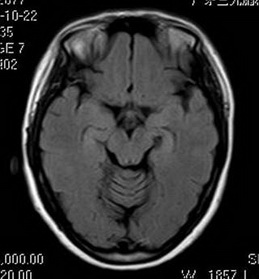

经神经外六科吴杰主任及其团队详细评估后,为小敏全麻下行“左前颞叶切除术”。术后,小敏恢复良好,至今未见癫痫发作。术后病理回报提示:1、(左前颞叶、左海马)形态结合免疫组化符合局灶皮层发育不良伴海马硬化;2、(左杏仁核)符合癫痫改变。

术后MR